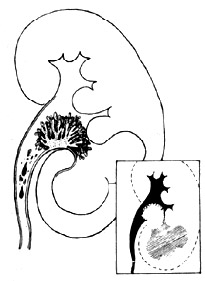

腎盂腫瘤2、逆行性泌尿系造影:其重要性為:

①造影更清晰,尤其是排泄性造影顯影不良時;

②可能見到病側輸尿管口噴血,下端輸尿管腫瘤向輸尿管口突出;

③直接收集病側尿行腫瘤細胞學檢查或刷取活檢;

④膀胱鏡檢查以除外膀胱內腫瘤。

逆行造影時,腎盂內注入過多對比劑可能遮蓋小的充盈缺損,輸尿管造影必須使全輸尿管充盈方可明確診斷。球狀頭(bulb)導管輸尿管造影,其輸尿管導管頭似橄欖或橡子塊,插入輸尿管口螢屏

腎盂腫瘤輸尿管腫瘤時可使以下導管彎曲或呈圈狀。如插管通過腫瘤可發現其上方為清尿,而導管旁邊流出的為血尿。

造影時必須防止帶入氣泡造成誤診。